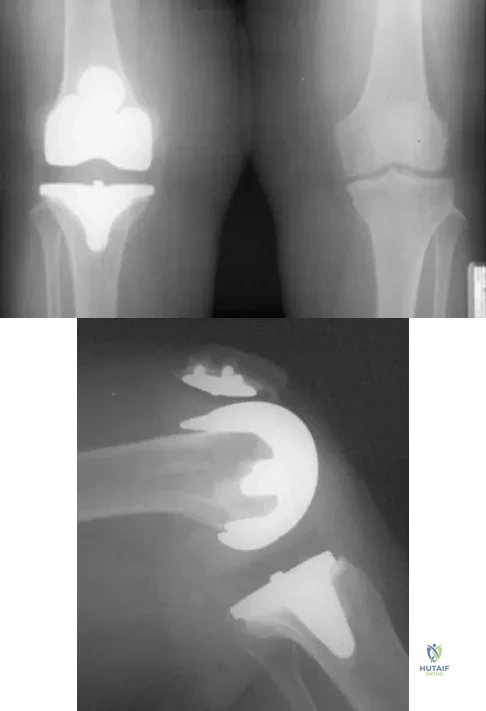

Question 82

A 63-year-old woman reports giving way of the knee and pain after undergoing primary total knee arthroplasty (TKA) 1 year ago. Examination reveals that the knee is stable in full extension but has gross anteroposterior instability at 90 degrees of flexion. The patient can fully extend her knee with normal quadriceps strength. Studies for infection are negative. AP and lateral radiographs are shown in Figures 12a and 12b, respectively. What is the appropriate management?

Explanation